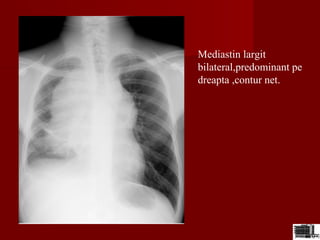

Mediastin largit

bilateral,predominant pe

dreapta ,contur net.